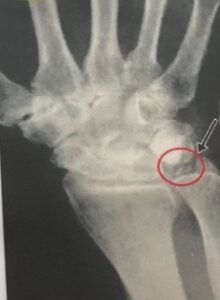

診断はレントゲン検査で関節軟骨にピロリン酸カルシウムが沈着することで、石灰化像が線状に認められます。他にも関節穿刺液検査で関節液内にCPPDの結晶が認められれば偽痛風の診断となります。

下記の写真は手関節の偽痛風レントゲン写真。⭕️部分が偽痛風です。